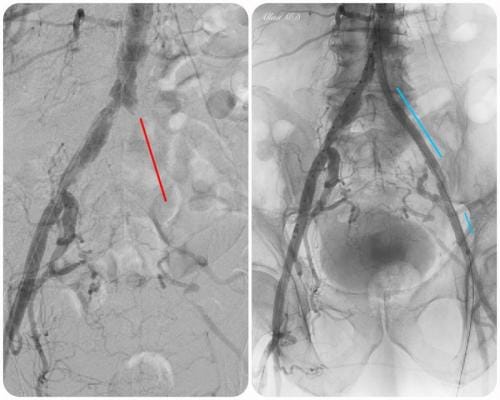

- What is the experience? Choose a specialist that has a proven record of tackling difficult cases successfully. Some specialist choose to only do the simple procedures and refer the rest to surgery. Additionally, if the specialist can only perform simple procedures they may have a higher rate of complication if the case turns out to be more difficult than expected. Our specialist has performed numerous successful complex procedures from the groin, knee and foot. See our prior cases here.

During these procedures: Sedation is given to help you relax. Next, a tiny tube is gently inserted in an artery, usually in the groin or upper thigh area. You will be given a local anesthetic to numb the area where the tube will be inserted. It is then guided through the blood vessel toward the disease artery. When it’s in place, a dye is injected through the catheter to visualize the arteries. An X-ray is taken to help the physician pinpoint the area that is blocked or narrowed. The physician then uses tiny wires and catheters to get through the diseased vessels. Depending on the images treatment may then be performed.

Angioplasty — a special catheter that has a balloon on one end is advanced into the diseased artery. This is temporarily inserted through the narrowed artery and inflated to flatten the plaque against the artery wall, opening the artery and restoring blood flow.

Stent placement —a stent is a small, expandable, leg pain angioplasty stent los Angeles san diegomesh-like tube that supports the artery and helps to keep it open. Implanting a stent does not require open surgery. The doctor inserts a catheter into an artery in your arm or leg, similar to the balloon angioplasty procedure. A specially designed catheter delivers the stent to the narrow area in the artery. The stent is expanded, flattening the plaque against the artery wall and holding the artery open with a mesh tube. The catheter used to deliver the stent is then removed, but the stent stays in your artery permanently to maintain healthy blood flow.

Atherectomy — a specialized catheter that modifies the plaque in the arteries. Unlike angioplasty and stenting, which are designed to move plaque to the sides, atherectomy involves cutting and removing or sanding down the plaque from the artery, restoring normal blood flow.